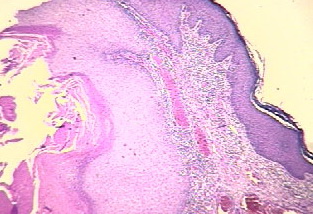

Kaposiform hemangioendothelioma =بطانوم وعائي دموي يشبه كابوزي OLYMPUS DIGITAL CAMERA OLYMPUS DIGITAL CAMERA OLYMPUS DIGITAL CAMERA Kaposiform Hemangioendothelioma KHE is a rare vascular tumor that has usually been reported in association with KMP. It may be present at birth or develop in early childhood. Rare adult cases have been reported. It may present as […]